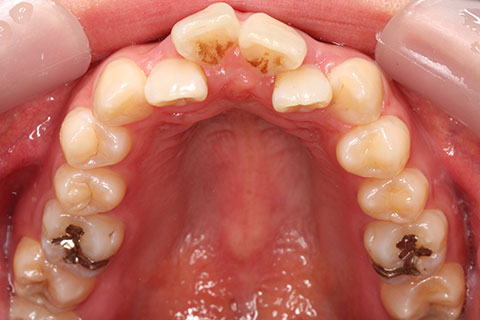

症例

治療前

治療中

治療後

- 年齢・性別

- 30歳女性

- 治療期間

- 3年0ヶ月

- 抜歯

- 上下左右4番抜歯

- 治療費

- 110万円

- 備考

- マルチブラケットを用いた矯正治療

- 治療内容

- 上下顎前突を4本抜歯にて矯正治療

- 施術の副作用(リスク)

- 表側矯正と比較して、歯根の角度を確立する「トルク」の力がかかりにくい。